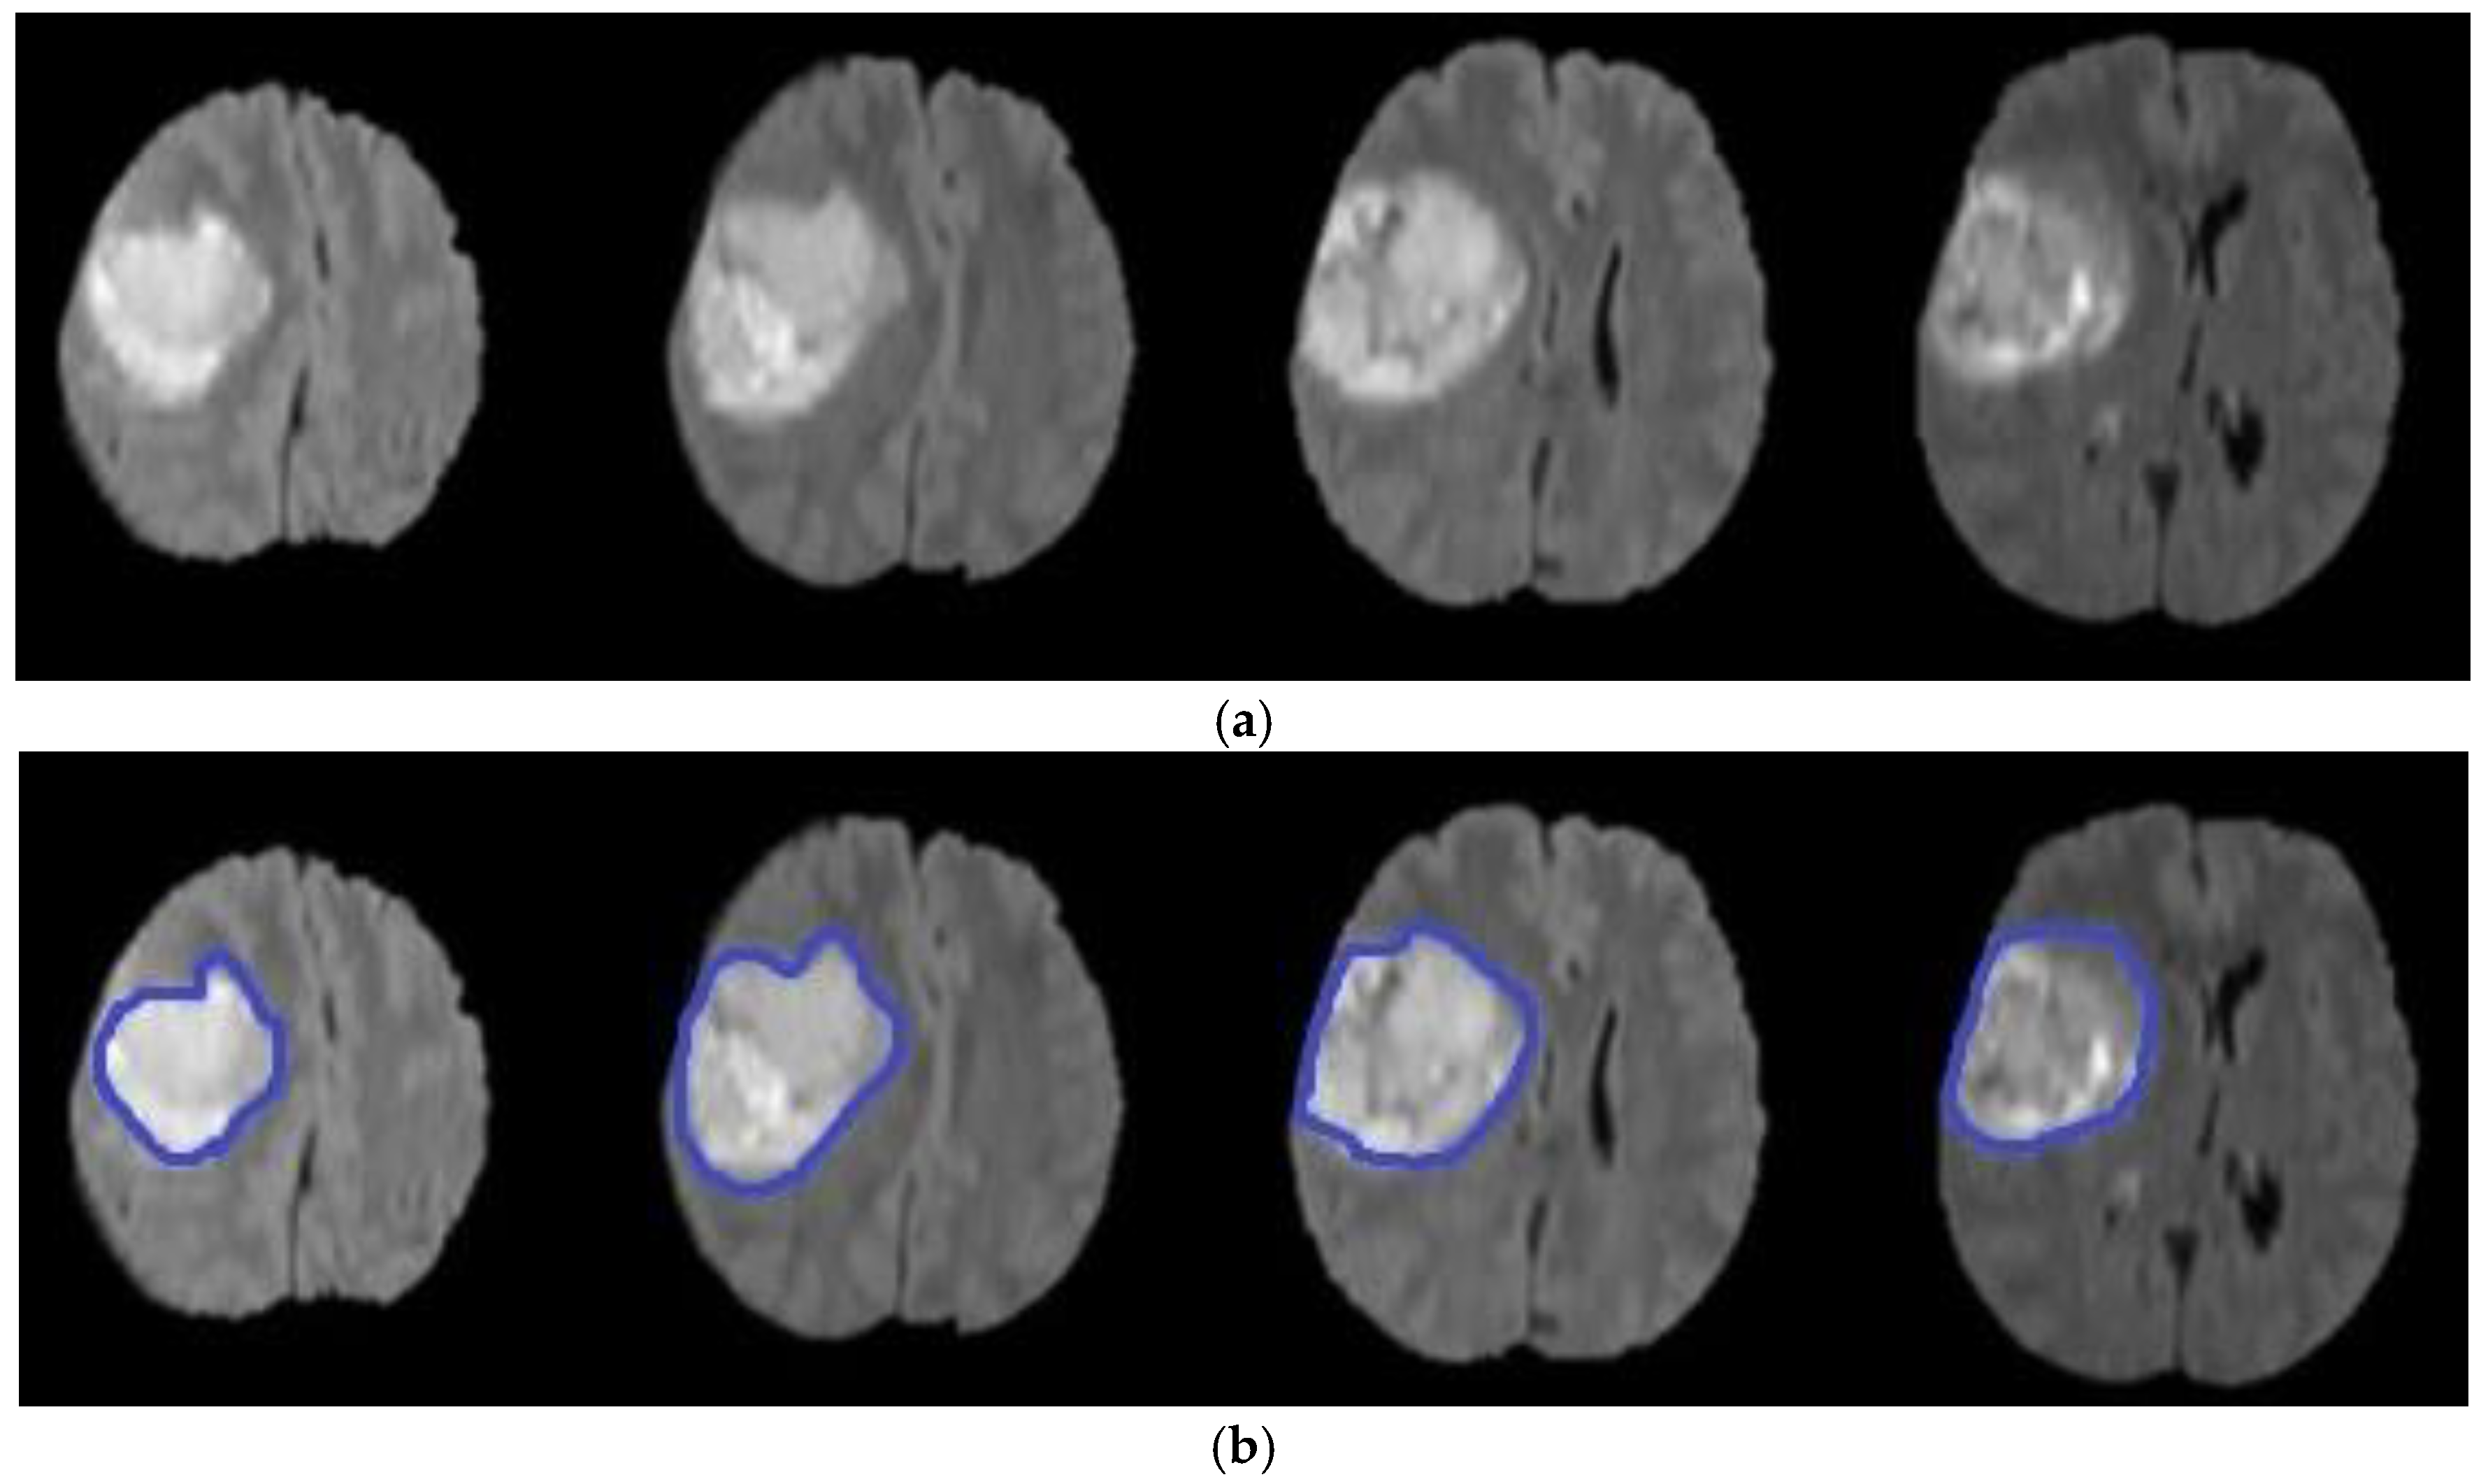

where is the evolution of , is the field for speed, is the normal interface vector, is a curvature controlled term with the parameter , is a velocity term weighted by , is equal to the scale of the image outline, and is the variance of the Gaussian . Finally, represent a local advection force that pulls the level set towards the tumor boundaries; this force is weighted by the parameter . After some repetitions of the PDE or once has converged, the final level set function is achieved. Algorithm 3 illustrates the main steps of the level set segmentation procedure. Figure 7 shows the result of applying the level set segmentation to a set of images.

Figure 7.

Brain tumor segmentation using level set (a) original images (b) segmented tumors.